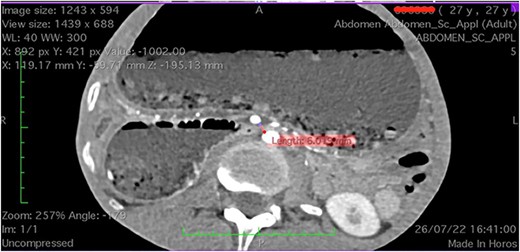

Upon admission, the patient was severely malnourished with a body mass index (BMI) of 15.7 kg/m2. On physical exam, his abdomen was softly distended and tympanic but non-tender. On chest auscultation, the patient had diminished breath sounds at the lower base of the right lung. He was transferred to the intensive care unit due to refractory shock and started on vasopressors and broad-spectrum antibiotics. A nasogastric tube was placed with an output of approximately 1.8 L of bilious content. After hemodynamic stabilization, computed tomography (CT) scan of the abdomen was performed, which revealed a distended stomach and first and second portion of duodenum (Fig. 1).

Computed tomography images showing a narrow aortomesenteric angle of 14.3° (sagittal section) and a massively dilated stomach, as seen on coronal and axial sections.

There was extrinsic compression of third portion of the duodenum by the SMA (Fig. 2).

Radiological findings are pivotal for the final diagnosis of SMA syndrome. A normal SMA and aorta artery angle ranges from 38 to 65°. Radiological criteria of SMA syndrome includes duodenal obstruction with rapid cutoff in the third part, aortomesenteric artery angle ≤25°, aortomesenteric distance ≤8 mm and abnormally high fixation of duodenum by the ligament of Treitz or low SMA origin [8].